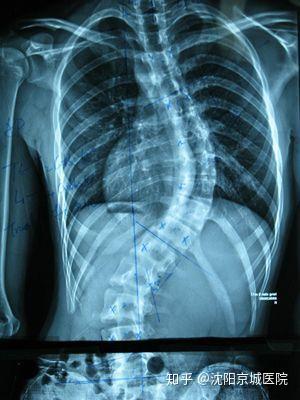

強(qiáng)直性脊柱炎的長(zhǎng)期影響可能包括脊柱的彎曲、后凸或側(cè)凸,這可能會(huì)影響到患者的身高和體態(tài),由于脊柱活動(dòng)度的降低,患者可能會(huì)遭受行動(dòng)不便的困擾,在嚴(yán)重的情況下,強(qiáng)直性脊柱炎可能會(huì)導(dǎo)致肺、腸道等內(nèi)臟器官的功能障礙,由于炎癥的影響,患者可能會(huì)出現(xiàn)貧血、骨質(zhì)疏松等并發(fā)癥。

早期診斷和干預(yù)對(duì)于控制強(qiáng)直性脊柱炎的癥狀和防止病情惡化至關(guān)重要,醫(yī)生通常會(huì)根據(jù)患者的癥狀表現(xiàn)、體格檢查和可能的影像檢查結(jié)果(如X光、MRI)來(lái)診斷強(qiáng)直性脊柱炎,治療的目標(biāo)主要是控制炎癥、緩解疼痛、防止病情惡化和提高生活質(zhì)量,治療方法包括藥物治療(如非甾體抗炎藥、免疫抑制劑等)、物理治療(如物理療法、按摩等)和生活方式調(diào)整(如運(yùn)動(dòng)、保持良好的姿勢(shì)等)。